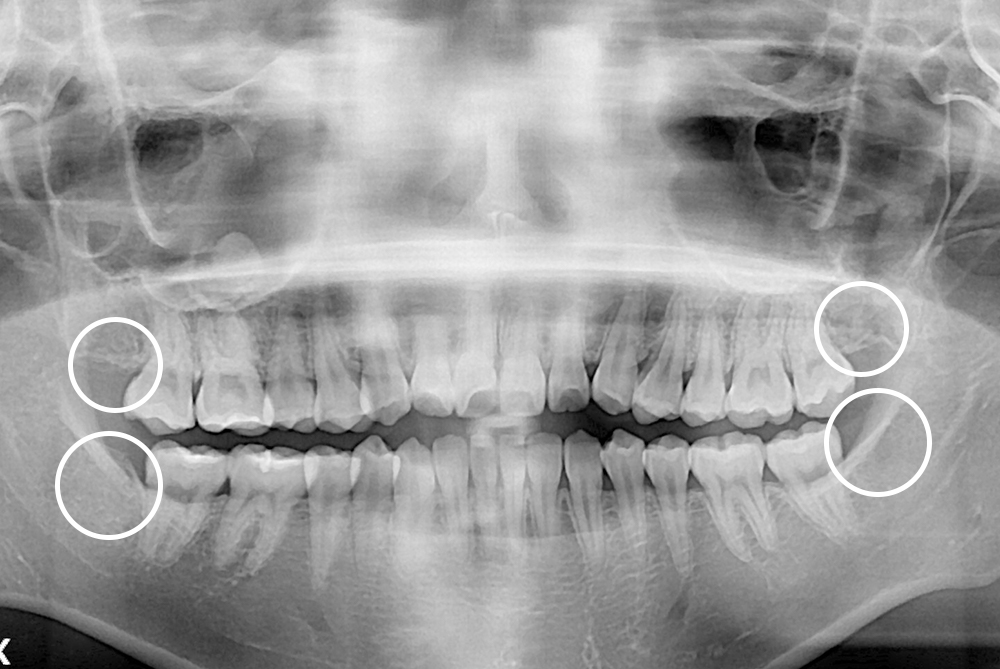

[사랑니] 매복 사랑니 발치

치료전 : 2018-08-20